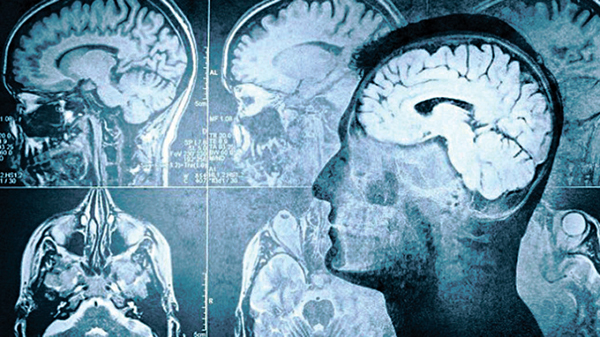

人類真正死亡的界定仍意見紛紜,德國一批神經病學專家則嘗試找出「真答案」;近日發表的研究發現,原來人類心臟停止5分鐘後,大腦或仍有意識,可短暫運作。預料研究有助醫護人員於日後作出相關診症及治療。

該批德國專家,早前在9名病危人士的腦部植入電極,研究他們瀕臨死亡邊緣時的腦部活動。

研究發現,當血液循環停止,原本控制離子分離的神經元開始失效,腦細胞會因缺氧而逐步動用「儲備能源」,此時便會出現「去極化」(depolarisation)過程,神經細胞會變得極度活躍,最後才突然沉寂下來。

但專家認為,神經細胞沉寂並不代表死亡,只是死亡倒數。有份參與研究的德賴爾解釋,去到離子釋放能量的步驟,雖然標誌病人正步向死亡,但此時若醫護人員能重新恢復病人的血液循環系統,將可在某程度上挽回病人的腦活動,但目前仍未知,大腦隨此之後還可維持運作多久。

今次的研究發現,預料將有助醫護人員作日後相關診症及治療,或會幫助醫護人員研發為心臟驟停,或中風病人恢復循環系統運作的新治療方法。